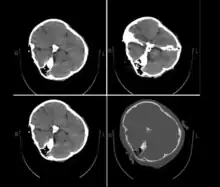

On 16 September 2022, 22-year-old Iranian woman Mahsa Amini,[lower-alpha 1] also known as Jina Amini,[lower-alpha 2][1][2][3] died in a hospital in Tehran, Iran, under suspicious circumstances. The Guidance Patrol, the religious morality police of Iran's government, arrested Amini for allegedly not wearing the hijab in accordance with government standards. The Law Enforcement Command of the Islamic Republic of Iran stated that she had a heart attack at a police station, collapsed, and fell into a coma before being transferred to a hospital.[4][5] However, eyewitnesses, including women who were detained with Amini, reported that she was severely beaten and that she died as a result of police brutality,[6][7][8] which was denied by the Iranian authorities.[9] The assertions of police brutality, in addition to leaked medical scans,[10] led some observers to believe Amini had a cerebral hemorrhage or stroke due to head injuries received after her arrest.[11]

Published hospital pictures show Mahsa Amini bleeding from the ear and with bruises under her eyes. In an 18 September letter, Doctor Hossein Karampour (the top medical official in Hormozgan province), pointed out that such symptoms "do not match the reasons given by some authorities who declared the cause to be a heart attack... (they are instead consistent with) a head injury and the resulting bleeding."[64] This was also confirmed by alleged medical scans of her skull, leaked by hacktivists, showing bone fracture, hemorrhage, and brain edema.[10][65]

By 21 September, the hospital had released preliminary CT scans. Government supporters stated the CT scans showed psychological stress caused by a previous brain operation; critics stated the scans showed physical beating and trauma. The Iranian government stated Amini had a brain operation at the age of five.[67]